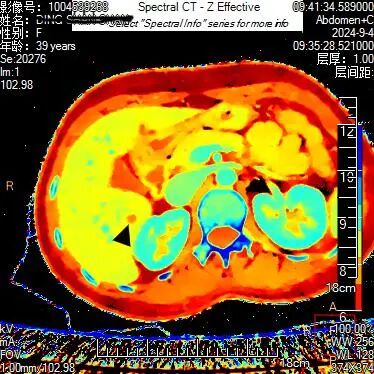

上腹部隐痛不适半个月,在当地医院就诊未发现明显异常,患者到贵州航天医院就诊,被检出肝脏肿瘤性病变,得到了及时诊治。 近日,一位39岁的女性患者在贵州航天医院就诊,通过该院最新引进的贵州首台飞利浦皓克双层探测器光谱CT,进行高精度扫描,该院医师利用光谱CT多参数能谱数据分析中的单能40KeV、碘密度图及有效原子序数功能,对患者进行了细致分析,医师在患者肝脏S6段发现一隐匿性肿瘤性病变,患者得以早期发现及时治疗。 采用光谱有效原子序数图 贵州航天医院医学影像科主任余雷向记者介绍,这个病例凸显了飞利浦皓克光谱CT对隐匿性肿瘤诊断的独特优势,其多参数光谱功能为医师提供了精确和更多的诊断依据,从而确保了患者病变的早期发现、得到及时准确的治疗。 余雷介绍,贵州航天医院为贵州省首家引进飞利浦皓克光谱CT,256排双层探测器的医院。皓克光谱CT扫描速度快、辐射剂量小,实时扫描既能产生光谱曲线、有效原子序列图、碘密度测量、尿酸及结石成分分析等16种不同参数的能谱数据图像,同时,在心血管、肿瘤、神经等系统的疾病准确诊断方面有其独特的价值,能够发现隐匿性肿瘤病灶,利用光谱曲线、碘定量测量等,可以准确分析肿瘤的良恶性,多发病灶的同源性;还能显示心肌缺血病灶,对血管斑块进行定量定性分析。 “目前,该设备已在我院放射科安装完成并投入使用。与传统CT相比,皓克光谱CT不仅提升了疾病鉴别诊断的准确性,还能指导临床个性化、精准化的治疗方案。”余雷介绍。 更多内容请关注遵义晚报视频号 ▼▼▼ 遵义晚报 4 审核:张小东 徐飞 责编 :胡笳